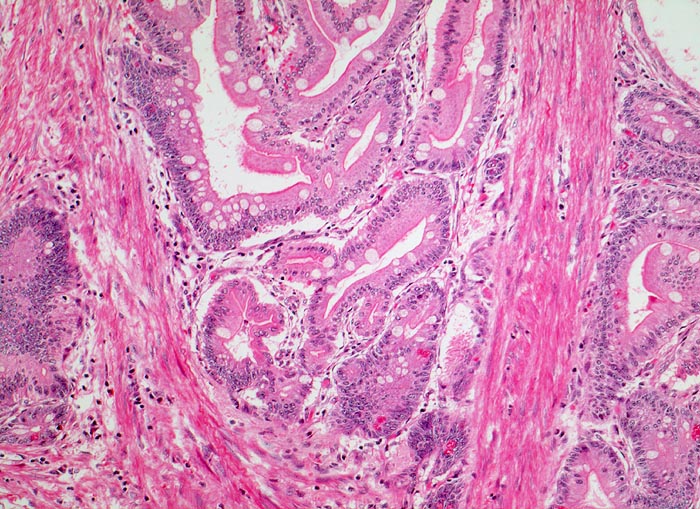

AP/ Peutz-Jeghers Polyp, Dünndarm

Peutz-Jeghers Polyp, Dünndarm

Jejunum

Pathologischer Befund